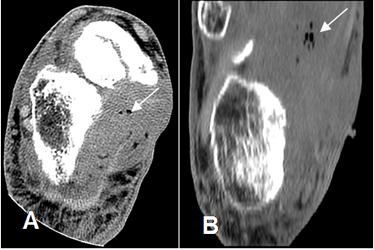

Fig 15. Fasceitis necrotizante.

A: TAC axial y B: TAC reconstrucción coronal. Prominencia de tejidos blandos y detección de burbujas de aire, por fasceitis necrotizante.